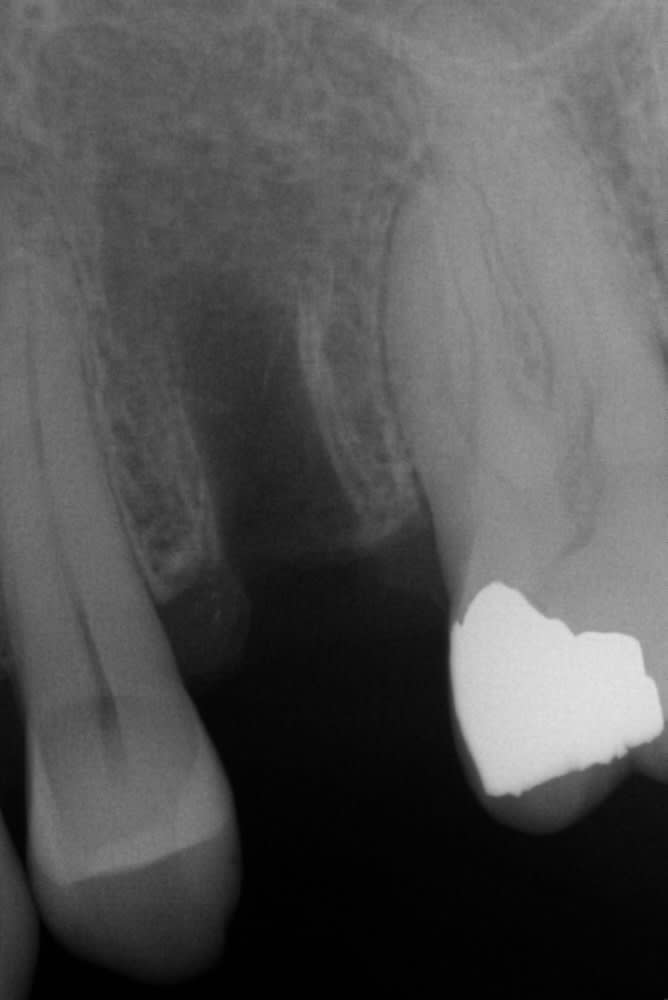

bonjour,

voici la radio de contrôle du patient a 2 ans.